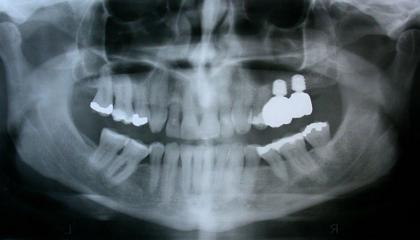

Zirconia bridge on Southern DC Implants